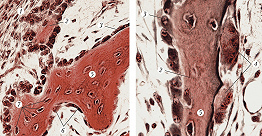

Существует два типа костной ткани – грубоволокнистая и пластинчатая. Грубоволокнистая ткань (рис. 2) характеризуется неупорядоченным расположением коллагеновых фибрилл и лакун с остеоцитами в матриксе. Она характерна для зародышей, у взрослых встречается редко, лишь в областях черепных швов, прикреплений сухожилий и участках заживления костных переломов. Образуется на месте эмбриональной мезенхимы (прямой остеогенез). Пластинчатая ткань (рис. 3) отличается большой прочностью, построена из осн. структурно-функциональных единиц – остеонов (Гаверсовых систем). Последние представляют собой неск. цилиндров, вставленных один в другой; их ось параллельна длинной оси К. На поперечном срезе остеона видно, что в его центре находится Гаверсов канал, в котором проходят мелкие кровеносные сосуды и встречаются камбиальные остеогенные клетки. Вокруг канала расположено неск. концентрич. пластинок матрикса. Между пластинками в лакунах залегают остеоциты с отростками. Эти отростки, проходя под прямым углом по узким щелевидным полостям в матриксе, пронизывают пластинки и соединяют щелевыми контактами остеоциты. С внешней и внутр. стороны пластинчатая К. окружена системой параллельно идущих костных пластинок, граничащих с надкостницей снаружи и с эндостом внутри К. Пластинчатая ткань широко распространена у позвоночных, составляя основу большинства К. скелета. Она формируется на месте хрящевой модели будущей кости путём непрямого остеогенеза – многоступенчатого процесса разрушения хряща и замены его (с участием остеобластов и остеокластов) грубоволокнистой, а затем пластинчатой костной тканью. Регенерация К. после её переломов осуществляется камбиальными остеогенными клетками, локализованными в надкостнице, эндосте и каналах остеонов. Эти клетки мигрируют в зону повреждения, здесь же пролиферируют и дифференцируются в остеобласты. Такой тип регенерации сходен с гистогенезом К. в эмбриональном периоде, с первичным образованием грубоволокнистой костной ткани и последующим её замещением (при соответствующих условиях) на пластинчатую ткань.